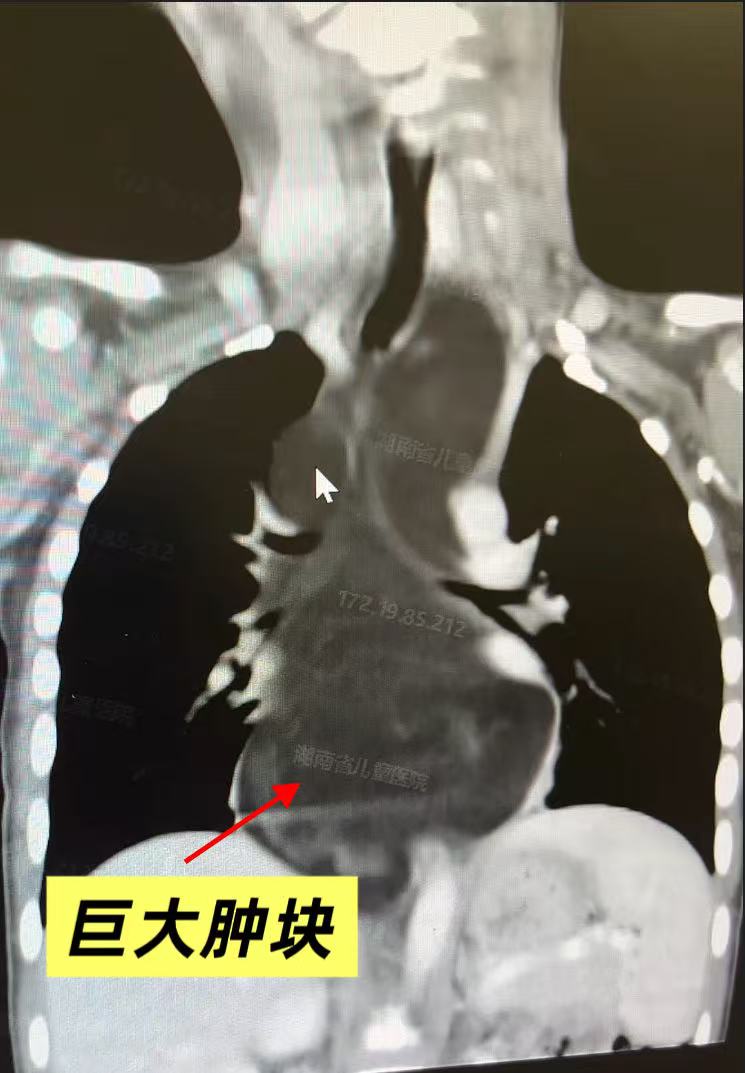

约十天前,小宇因受凉后反复低烧,在当地医院检查时,胸部CT发现右侧纵隔内有一巨大肿物,当地医院评估手术风险极高,建议转诊上级医院,一家人紧急来到湖南省儿童医院心胸外科门诊就诊,“门诊一看片子,我们心里就有数了,这东西不小,而且位置很深。”心脏中心一病区主任医师阳广贤回忆道,“纵隔是胸腔内心脏、大血管、气管、食管等重要器官的“集中地”,这个地方一旦长东西,不管良性恶性,都像在“心脏门口堆家具”——不是什么好事。”但这个直径约 15厘米的巨大肿物,呈分叶状,已经在他小小的胸腔里“扎根””,紧紧包裹着奇静脉弓、向后压迫食管、迷走神经,向前压迫气管及心脏,向下延伸至膈肌水平,部分侵入了左侧纵隔深处、主动脉后方,随时可能压迫加重导致窒息、手术刻不容缓.

巨大的肿块